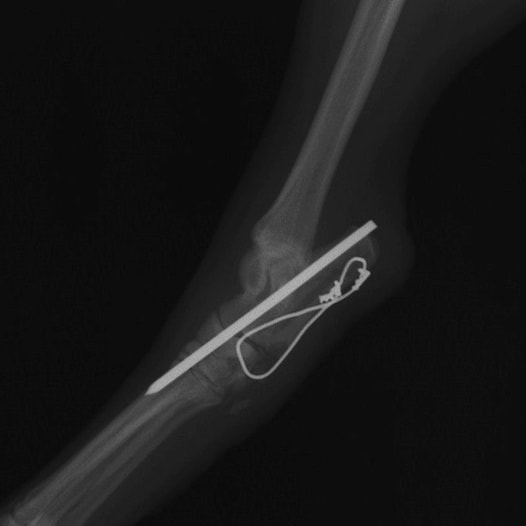

症例:柴犬 3歳

左後肢の完全挙上を主訴に来院されました。触診にて近位足根関節の過伸展を、レントゲン検査にて左足根関節周囲の軟部組織の腫脹、ストレス撮影によって距骨・踵骨と第4足根骨・中心足根骨間の脱臼および過伸展を認めました。

術中において、浅趾屈筋腱を剥離、内方へ牽引し、直接踵骨から第4足根骨までピンを挿入し(あらかじめ細いピンで下穴をあけておくとよい)、テンションバンドワイヤー法を併用し、関節軟骨の掻爬と海綿骨移植を実施しました。

術後レントゲン画像上に癒合が認められるまで約2ヵ月間は、運動を制限する必要があります。

術前側面像屈曲位